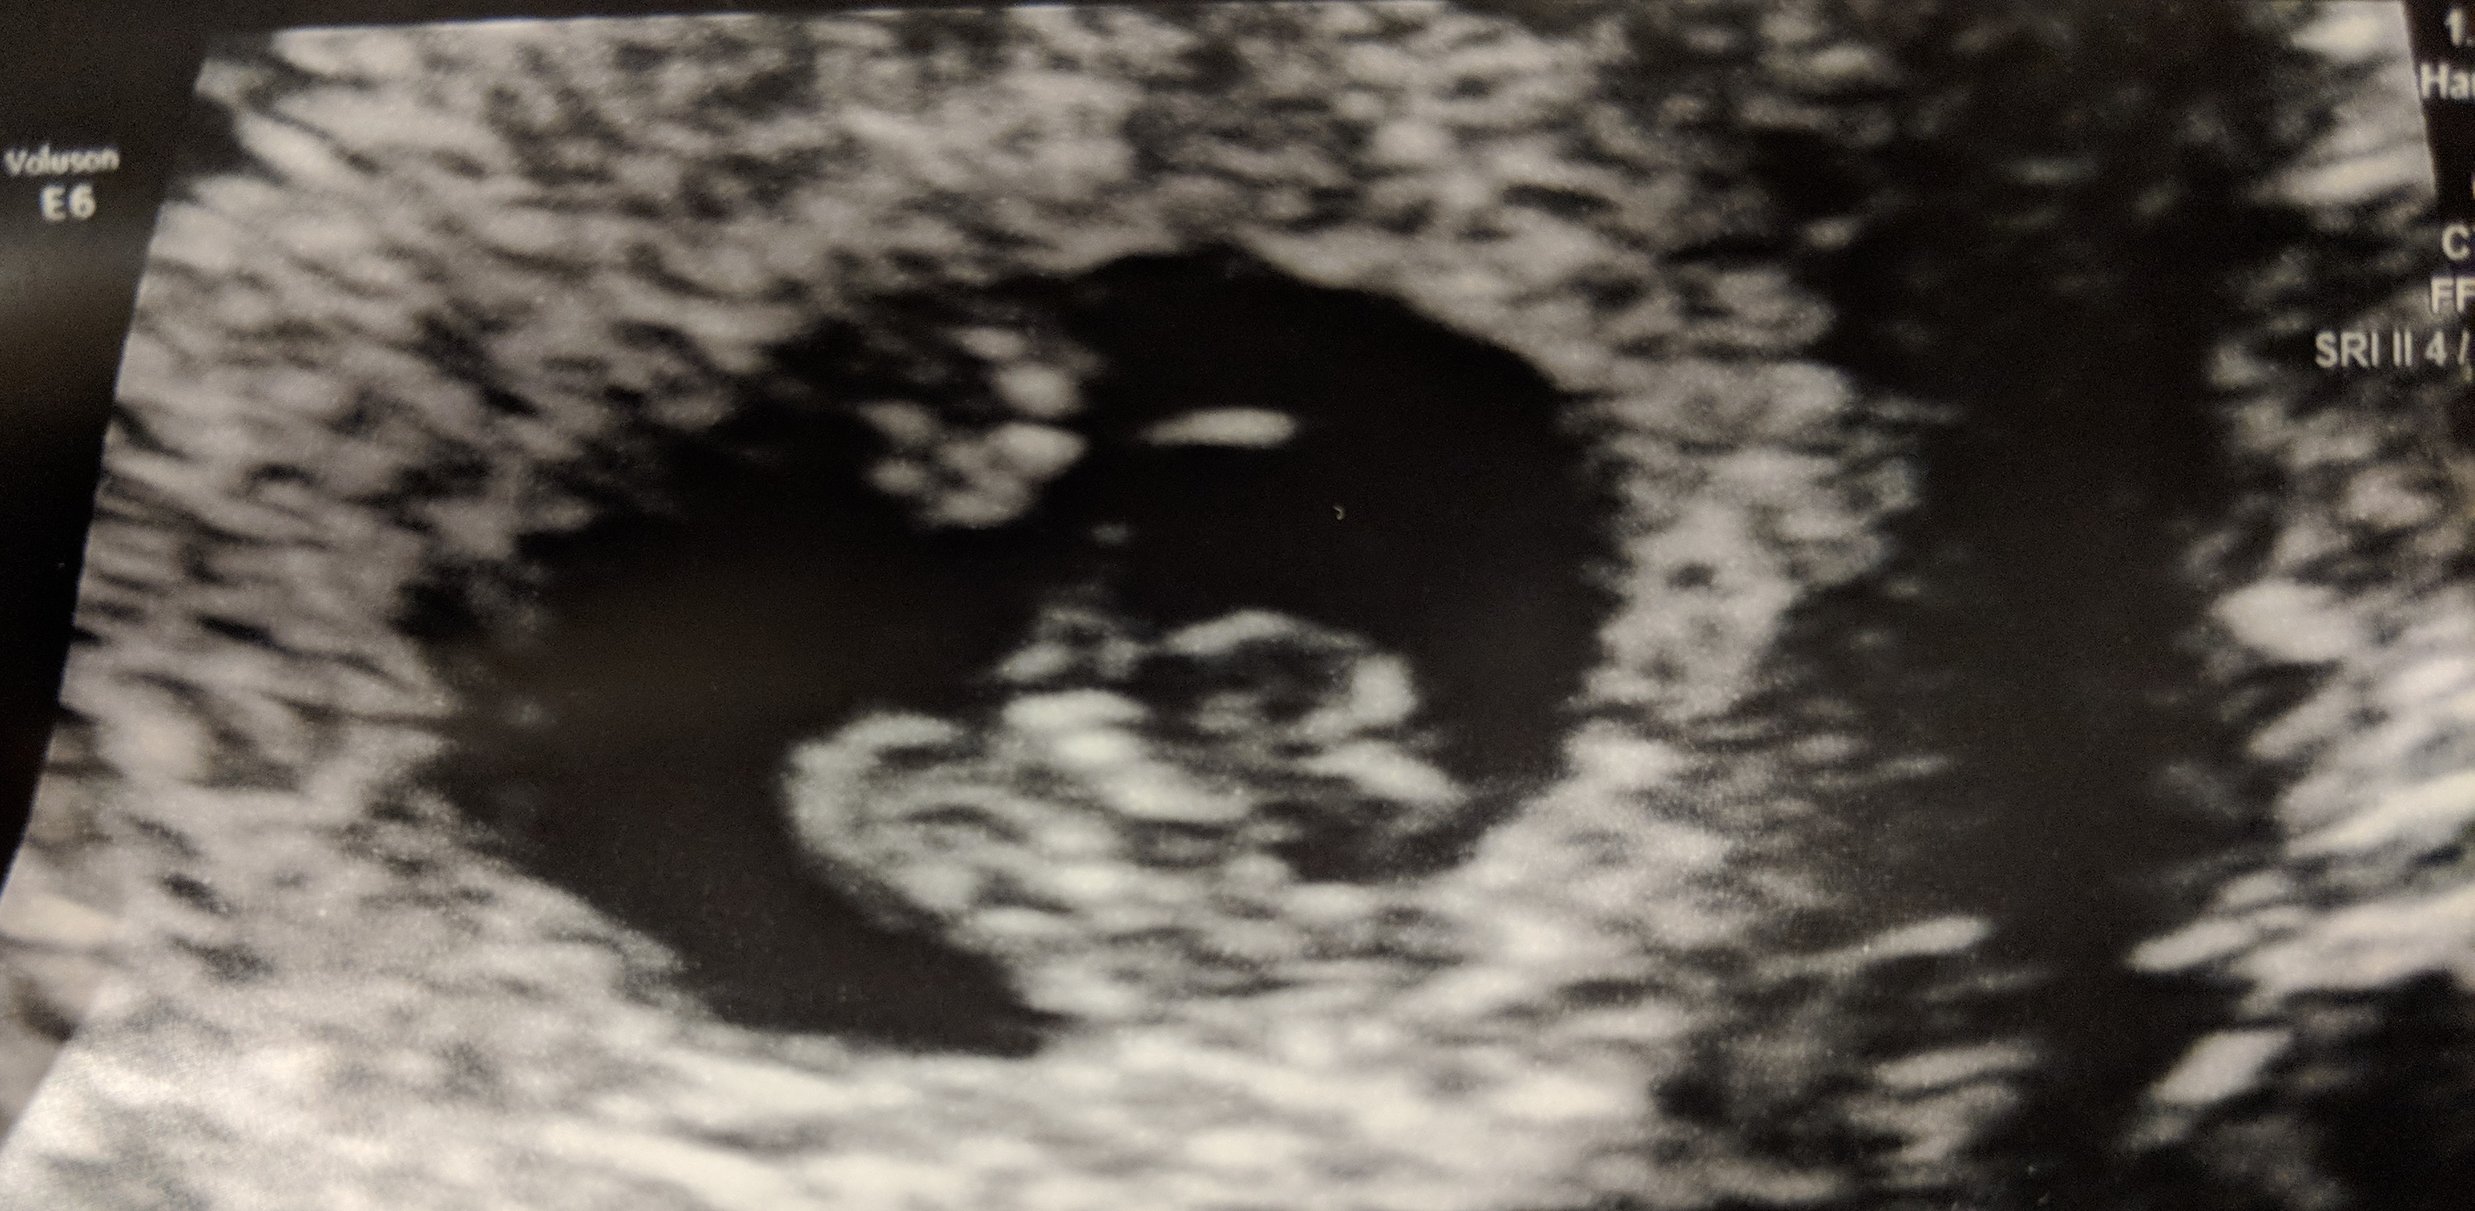

Hi everyone, 6 weeks ultrasound. I’m scheduled back for an 8 weeks ultrasound. Doctor said it’s twins but one is smaller than the other one that we had to wait and see if the other progresses. Has anyone had a similar situation? This is my 3rd pregnancy but first time twins.

• I had my first ultrasound on Monday! I'm not as far along as I thought - I thought I was past 10 weeks but I'll be just 10 weeks tomorrow. So glad I decided to have an early ultrasound - last pregnancy I just had one at 20 weeks. This time around I was having cramping and bleeding and something seemed off. I guess this is why!!!! Seeing double!! They think identical but can't quite be certain yet as I only wanted an abdominal ultrasound this visit. Needless to say I'm freaking out! New due date of November 8th instead of the 3rd...but I'm sure with twins it may be October!